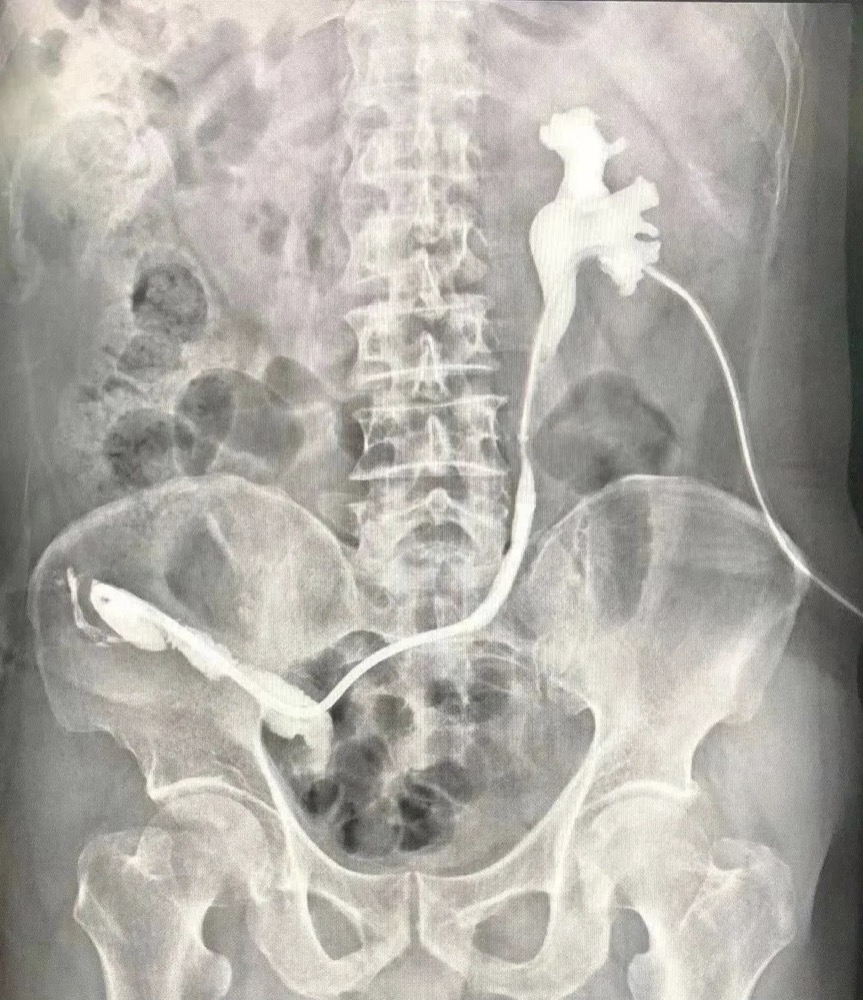

患者影像资料。

几年前,张爷爷因腰痛、发热、血尿等症状去医院检查确诊为膀胱癌,并接受了全膀胱根治术+回肠输出道术,术后需留置输尿管支架管。但在留置期间,张爷爷反复出现肾积水、输尿管扩张并伴有发热等感染症状,在定期更换输尿管支架管后效果仍然不佳,为此,张爷爷的家人带着他辗转求医,但感染症状仍未得到缓解。得知武汉同济航天城医院有武汉同济医院专家长期驻诊,于是家人带着老人来到该院就诊。

在完善术前检查后,该院泌尿外科团队进行术前讨论,根据老人的身体条件制定了温控记忆合金输尿管支架治疗输尿管-回肠吻合口狭窄的手术方案,手术由该院院长曾晓勇教授主刀,利用温控记忆合金输尿管支架技术,结合输尿管软镜技术,为张爷爷解除了输尿管-回肠吻合口狭窄,解决了困扰他多年的肾造瘘问题。目前,张爷爷恢复良好,并于9月6日顺利出院。